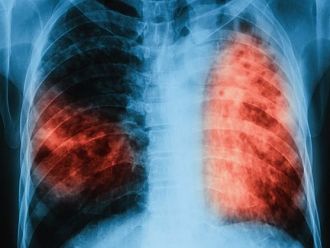

Изониазид се използва за лечение на всички форми на активна белодробна туберкулоза, всички форми на активна извънбелодробна туберкулоза, мултирезистентна туберкулоза, латентна туберкулоза и за химиопрофилактика на туберкулозата.